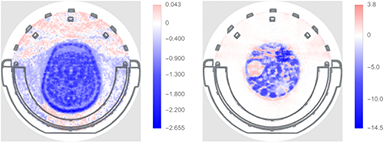

Image reconstructions comparing standard-coil-AC to Lu-coil-AC for the three subjects are shown in figures 13 and 15. Figures from an additional FDG exam are provided in the supplementary data (stacks.iop.org/PMB/63/035039/mmedia). In all three cases, faint streak artefacts that are visible in the images with standard-coil-AC are slightly reduced by using Lu-coil-AC. This is noticed, in particular, for the image reconstruction of the FET examination (figure 13). The different strengths of the weak streak artefacts and their location in the image can be easily seen in the corresponding difference images. The difference images are overlaid by the concentric ring artefacts previously mentioned, e.g. Badawi and Marsden (1999) and references therein, and are apparently not a consequence of the attenuation correction methods used. The concentric ring artefacts are not discerned in the transversal slices of the head and phantom images. Figure 14, left, shows the same image as figure 13, bottom left, but with a modified colour range and overlay of the head coil CT image for better visualisation and localisation of residual artefacts. For comparison, the difference between the ground truth phantom image and the phantom image with the coil but without coil AC is shown in figure 14 to the right (averaged over all image planes). A further important observation is that the estimated activity concentration is systematically higher for image reconstruction with the standard-coil-AC than for reconstructions with the Lu-coil-AC. The slightly increased image noise, as expected from table 3, is hardly noticeable in the head images reconstructed with the Lu-coil-AC. These three observations are in agreement with the findings in section 3.4. Except for the bias of the activity concentration, which can be compensated by recalibration of the Siemens 3T MR-BrainPET insert with the Lu-coil-AC, the observed differences in both AC methods are too small to be clinically relevant.

Figure 13. Transversal slice (left), coronal slice (mid), and sagittal slice (right) of first subject (FET). Upper row shows images reconstructed with standard-coil-AC. Middle row shows images reconstructed with Lu-coil-AC. Lower row shows difference images between Lu-coil-AC and standard-coil-AC.

Standard image High-resolution imageFigure 14. Left: overlay of CT image of the Tx/Rx head coil and the difference head image shown in figure 13, bottom, left with modified colour range for better visualisation of residual artefacts. Right: overlay of CT image of the Tx/Rx head coil and the three compartment phantom (difference between ground truth and image without AC, averaged over all planes of the phantom) with modified colour range for better visualisation of residual artefacts. Colour scale is in kBq  .

Standard image High-resolution imageFigure 15. Transversal slice (left), coronal slice (mid), and sagittal slice (right) of third subject (FDG). Upper row shows images reconstructed with standard-coil-AC. Middle row shows images reconstructed with Lu-coil-AC. Lower row shows difference images between Lu-coil-AC and standard-coil-AC.